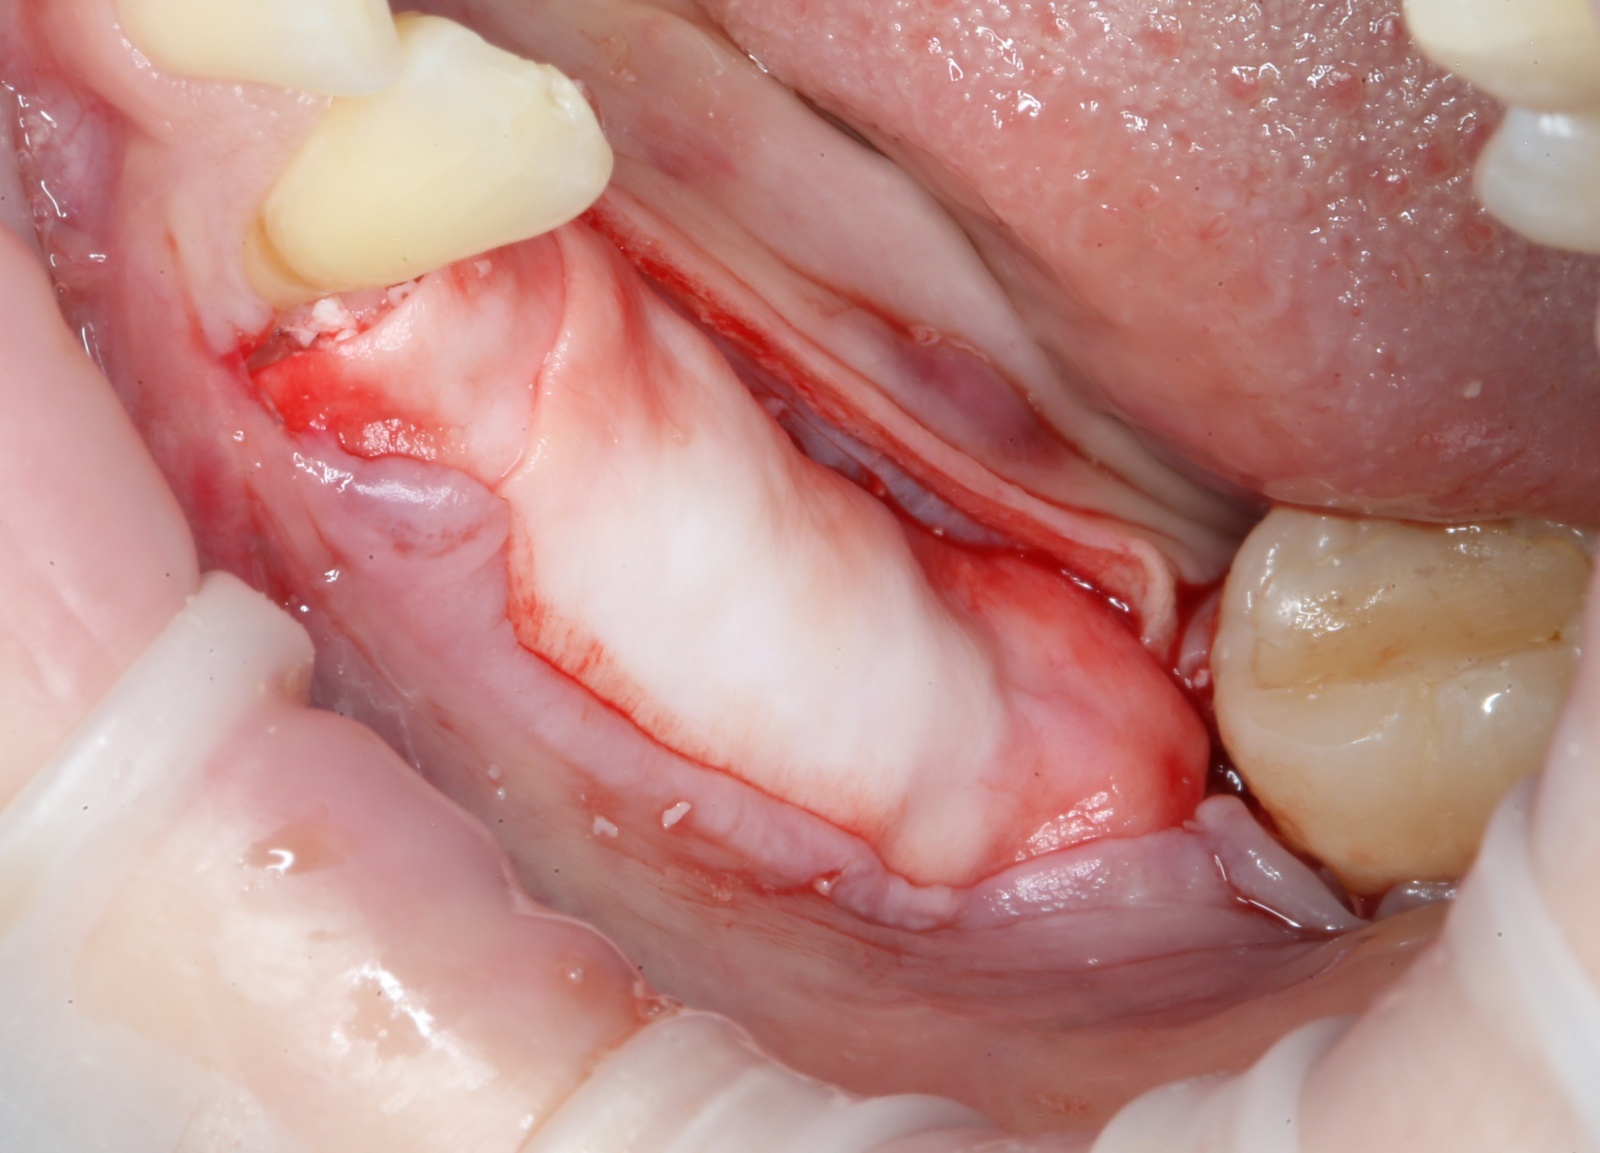

Время накладывать швы (ножницы и иглодержатель):

Используется шовный материал – монофиламент. Нерассасывающаяся нитка, наподобие лески. В отличие от рассасывающихся швов, эта нить не скапливает на себе налет и остатки пищи, что особенно важно в случае с операциями.

Операция закончена: